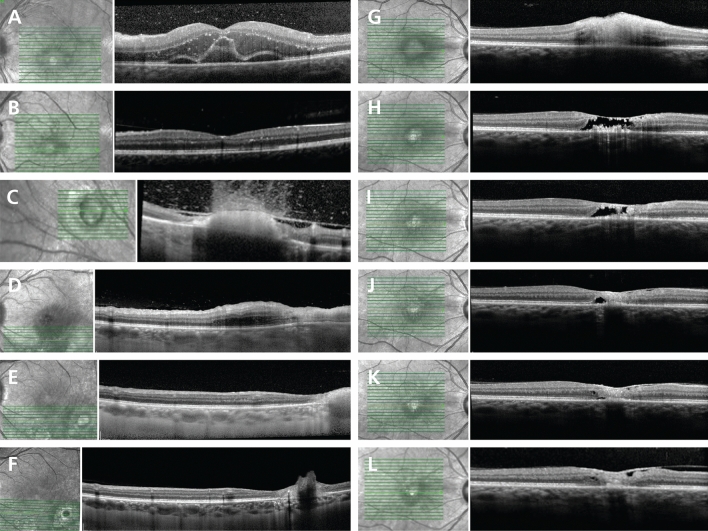

Figure 1.

Representative signs of active toxoplasmic retinochoroiditis by spectral domain optical coherence tomography. (A) Hyperreflective dots in the vitreous cavity overlying the optic disc (zone 1, primary, IgM-negative); note perivascular hyperreflectivity (arrow); (B) Large hyperreflective deposits (190 µm) at vitreoretinal interface (zone 2, recurrent, IgM-negative); (C) Hyperreflective blood vessel (circled, identified on en-face image) within a hyporeflective retinal space (HIV-positive, zone 2, recurrent, IgM-negative); (D) Intraretinal hyperreflective dots in the outer plexiform and outer nuclear layers (zone 2, primary, IgM-positive); (E) “Ribbon” appearance of hyporeflective outer nuclear layer between thickened hyperreflective photoreceptor-RPE complex and hyperreflective inner nuclear layer (zone 1, recurrent, IgM-negative); (F) RPE “bumps” (arrows), (HIV-positive, zone 2, recurrent, IgM-negative); (G) Hyperreflective dots in the vitreous cavity, thickened posterior hyaloid with partial posterior vitreous detachment; retinal thickening with full-thickness hyperreflectivity and adjacent disorganization of the retinal layers; adjacent RPE thickening, choroidal hyporeflectivity and thickening (zone 2, primary, IgM-negative); (H) Large hyperreflective deposit on posterior hyaloid face (zone 2, recurrent, IgM-negative); note thickened hyperreflective retina with choroidal hyporeflectivity and thickening; (I) Hyperreflective dots surrounding choroidal vessel (circled); hyperreflective dots on internal limiting membrane and disorganized retinal layers (zone 2, recurrent, IgM-negative); (J) Gross macular thickening with hyperreflective dots and intraretinal fluid in the outer plexiform and outer nuclear layers, subretinal fluid and bowing of RPE-Bruch’s membrane complex (zone 1, primary, IgM-negative); (K) Subfoveal fluid and hyperreflective dots in the vitreous cavity overlying a blood vessel (circled) (zone 2, primary, IgM-negative); (L) Round body in outer nuclear layer (circled), with adjacent retinal hyperreflectivity and disorganization of retinal layers (zone 2, primary, IgM-positive); (M) Subfoveal fluid with hyperreflective retinal dots, outer plexiform and outer nuclear layer fluid and hyperreflective dots, retinal hyperreflectivity, bowing of RPE-Bruch’s membrane complex, overlying hyperreflective dots in the vitreous cavity and partial separation of posterior hyaloid (zone 2, primary, IgM-negative); (N) Hyperreflective dots in the vitreous cavity, disorganization of retinal layers, RPE thickening with subjacent choroidal hyporeflectivity and adjacent subfoveal fluid (zone 1, recurrent, IgM-negative). Abbreviations: SD-OCT = spectral domain optical coherence tomography, TRC = toxoplasmic retinochoroiditis, Ig = immunoglobulin, RPE = retinal pigment epithelial/epithelium, HIV = human immunodeficiency virus.